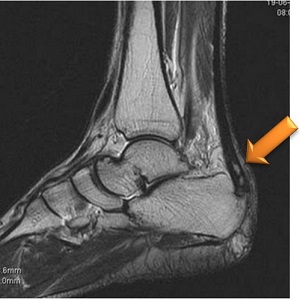

Самым информативным методом является МРТ-диагностика. При проведении данного обследования можно поставить точный клинический диагноз и исключить другие болезни (например, артрит, туберкулез костей, фасциит, бурсит, подагру и другие).

При рентгенологическом исследовании врачи отмечают ряд признаков:

- неоднородная или пятнистая структура пяточной кости;

- в костной ткани определяются очаги разрежения (уменьшения плотности ткани);

- определяются пятна из солевых отложений;

- смещение краевых костных фрагментов;

- образование щели между костью пятки и апофизом.

Нормальный пяточный бугор должен быть однородным с 3 или 4 ядрами окостенения, разделенными хрящевыми пластинками.